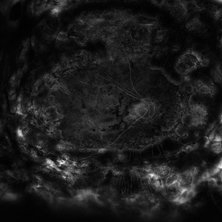

Composite fluorescein angiogram of the left eye of a man with Coats Disease.

Photographer: Olivia Rainey

Imaging device: Heidelberg Spectralis

Condition/keywords: Coats' disease, composite, fluorescein angiogram (FA), fluorescein leakage, Heidelburg Spectralis